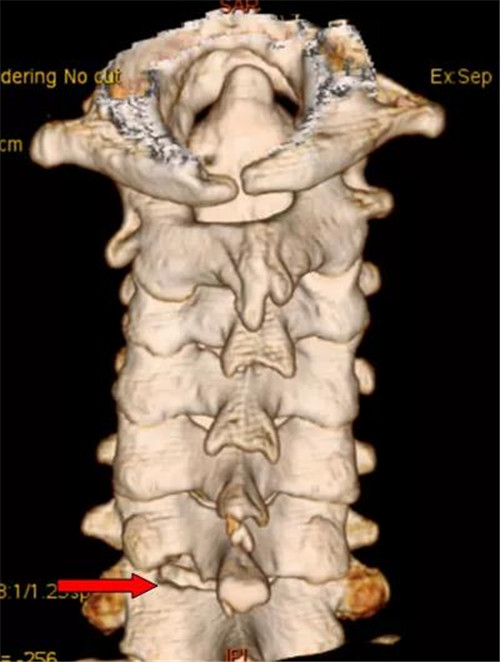

技术示意图(左)和术后复查三维CT

由于入院后的检查显示血糖指数过高,经过几天的休养陈大爷将血糖调到了正常值。9月7号,潘磊主任医师主刀、王诗成副主任医师、焦伟东医师协助为他实施了微创手术,一个小时后,成功将压迫神经的部分取出,手术顺利完成。“刚做完手术就感觉手已经不麻了!”,第二天下午,陈大爷已经可以下地走动。